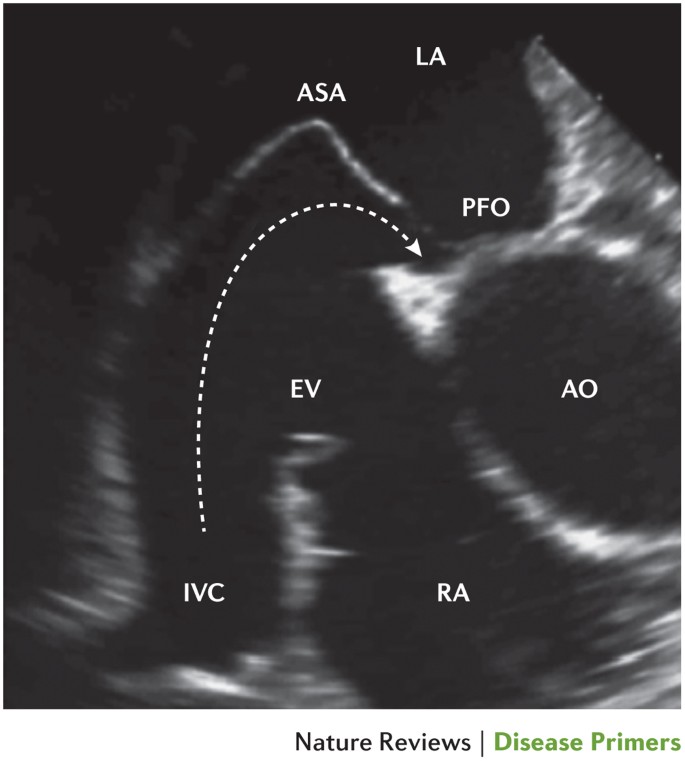

pfo medical term sale